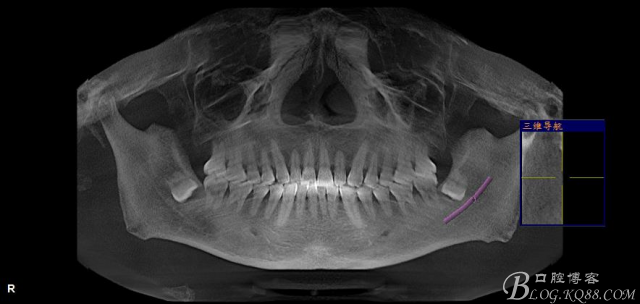

一、術(shù)前CBCT影像資料